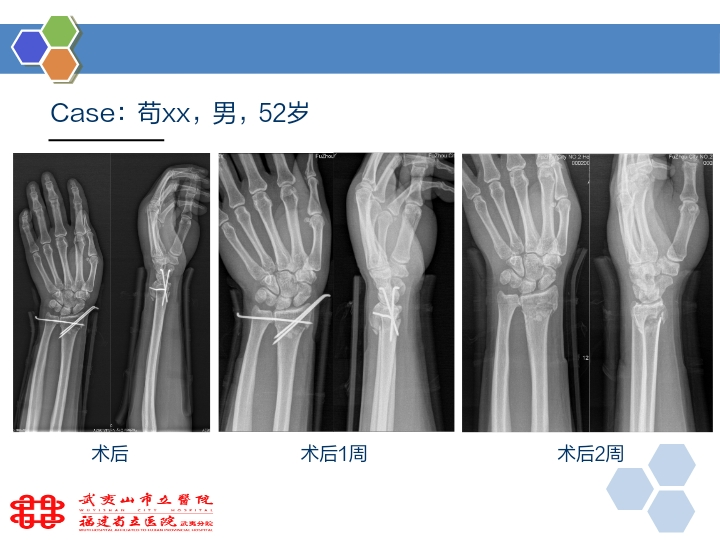

桡骨远端骨折的微创手术方法